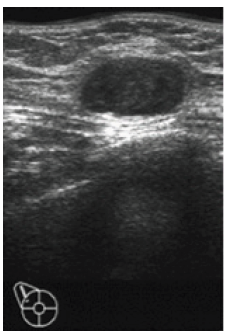

A 58-year-old woman complained right breast pain. We palpated a tumor in the right breast of the upper outer quadrant, 2cm in diameter, oval shape and elastic soft in texture. The US showed a mass, oval and smooth, clearly bordered, suggesting a fibroadenoma (Figure 1).

Note*: Oval and smooth, clearly bordered, suggesting a fibroadenoma.